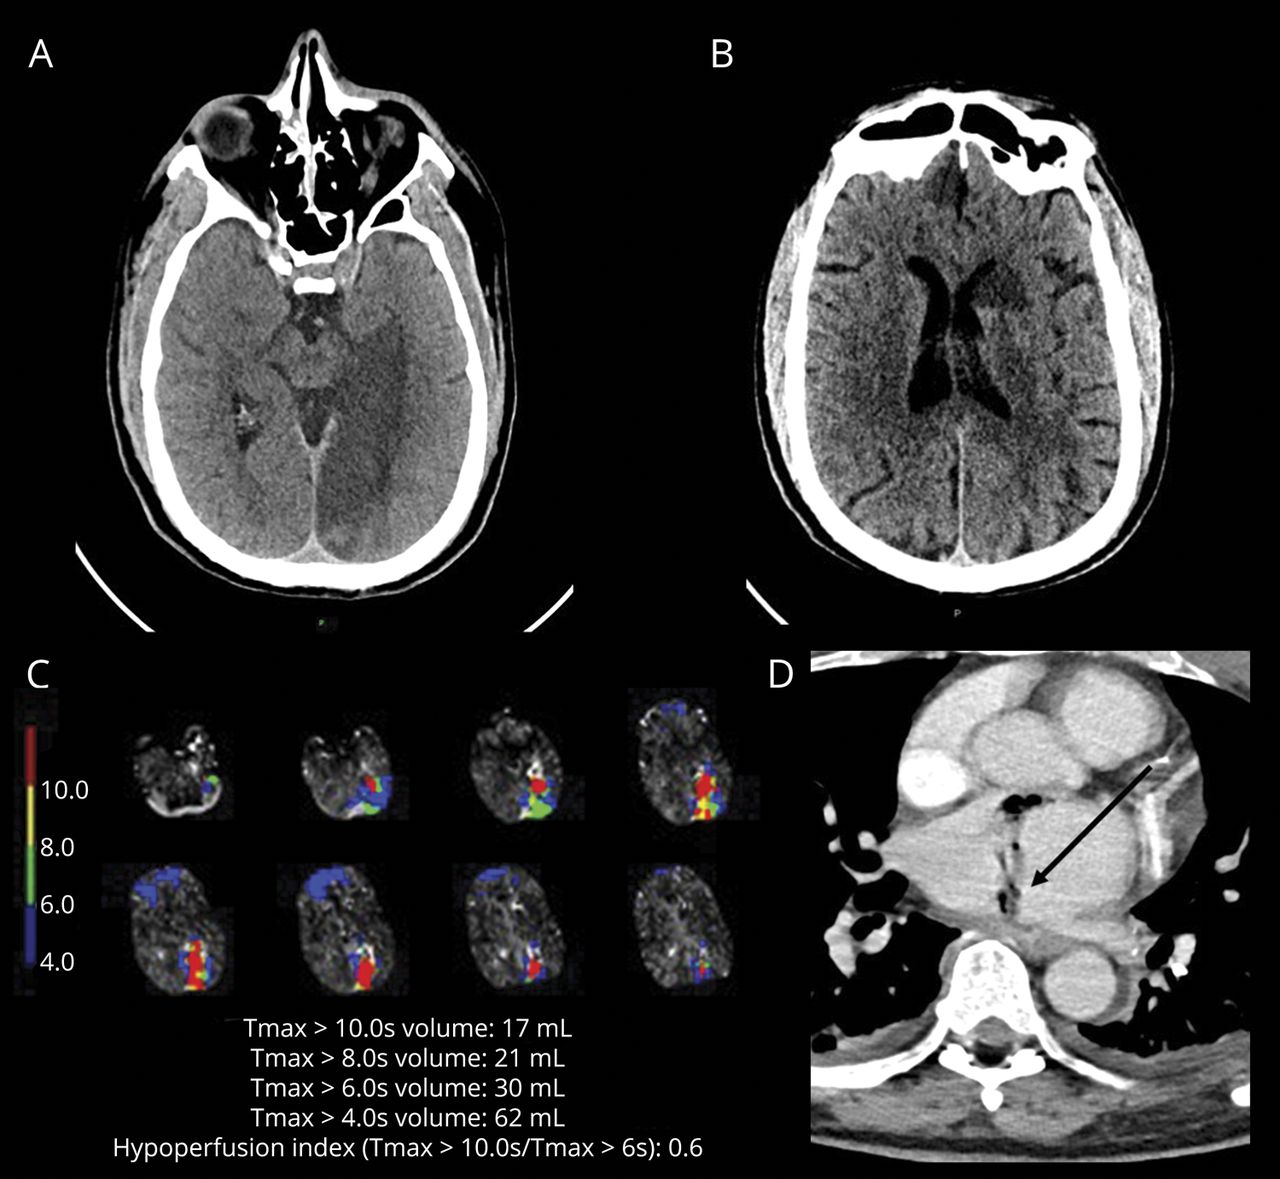

一个68岁的老人出现发烧和改变精神状态4周后心房颤动(房颤)的烧蚀过程。头部CT显示多病灶的embolic-appearing梗塞。胸部CT显示空气在左心房附件(图)。这些发现导致cardioembolic中风二级诊断脓毒性栓子atrioesophageal瘘AEF)。时可能发生在0.25%的房颤消融和体现1 - 6周postprocedure发烧、中风、终末器官的损害和/或脓毒性栓子。1经胸廓的超声心动图和胸部CT应考虑排除时患者的神经功能下降后房颤消融。1,2

选定的头部和胸部成像

轴头CT显示多病灶的脑梗塞(A)左侧颞枕叶和(B)基底神经节,(C) CT灌注(快速、Ischemaview,红木,CA)显示在多个血管灌注不足地区,空气和(D)轴向胸部CT显示在左心房和左心室附属物(箭头所指)。